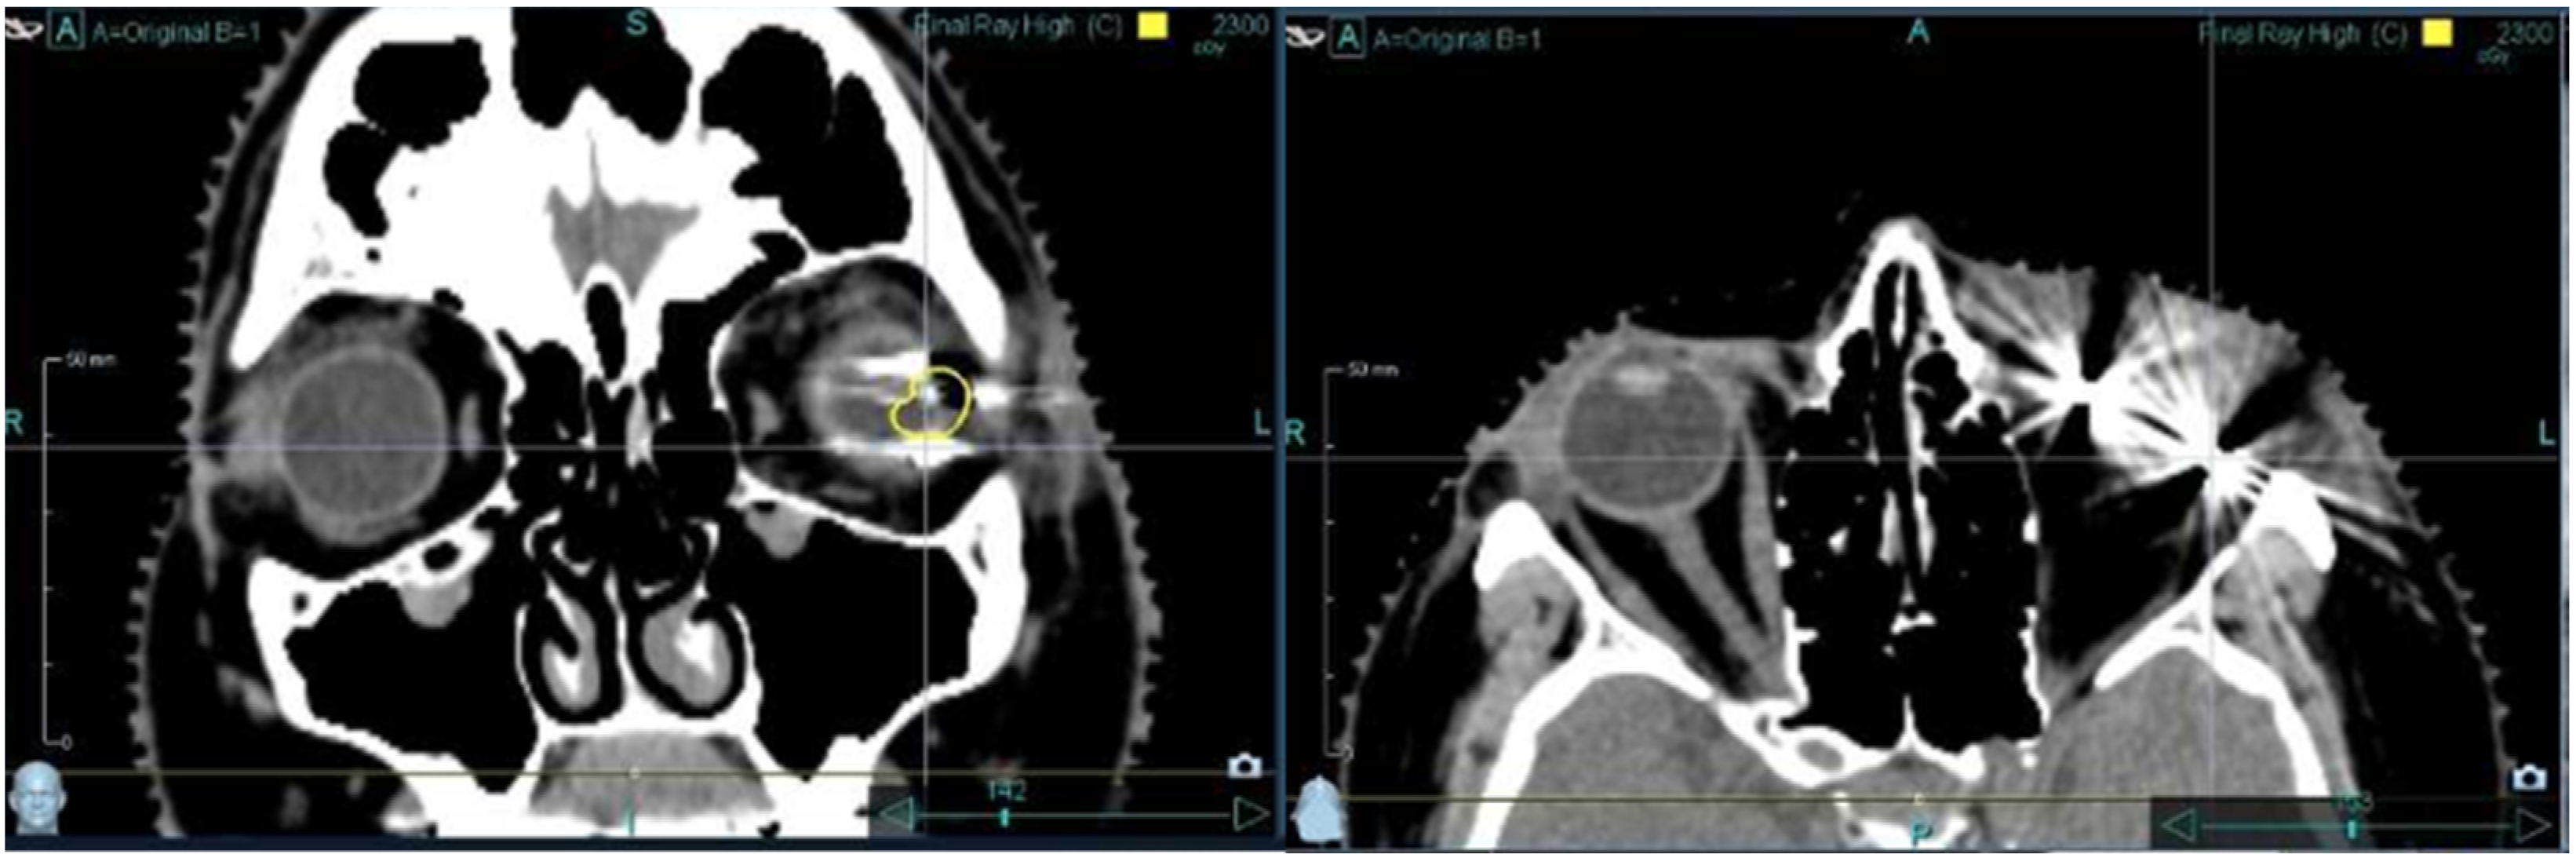

3.2. Imaging-Related Findings

3.3. Stereotactic Radiosurgery